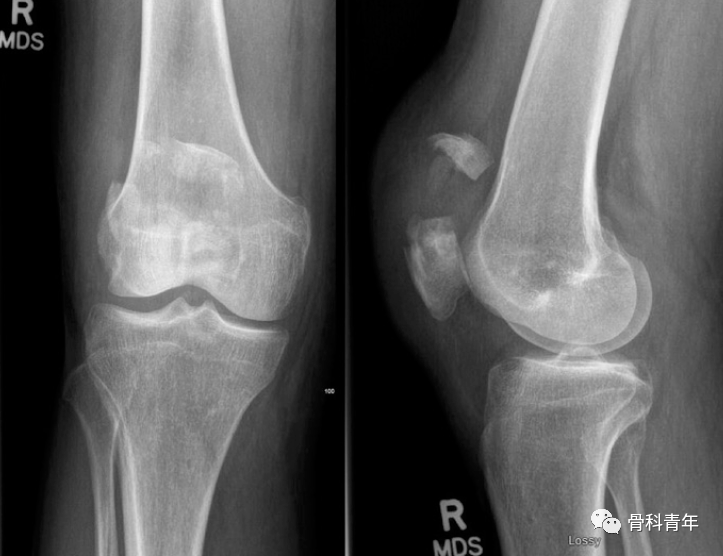

关于髌骨横行骨折,尽管在X线上较多髌骨均可见横行骨折线,但CT检查可发现仅有16%的髌骨骨折为单纯的横行骨折。这提醒我们在复位过程中,不应只关注于横行骨折线的复位,周围的骨折线也应注意到,并精确复位。

CT扫描可见髌骨骨折粉碎,四周骨折线在X线上显示不清晰。